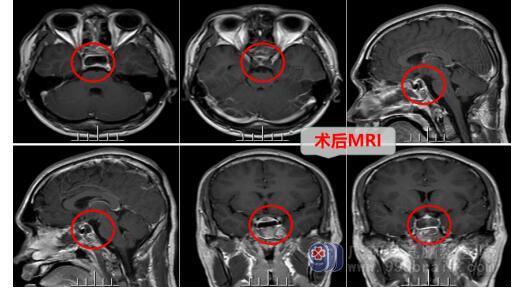

确定了病因所在,神经外十科医生团队对治疗方案、手术方案及要点进行详细的讨论及分析,选择行内镜下经鼻蝶鞍区Rathke’S囊肿切开引流术,手术顺利。术中垂体及视神经等保护良好。术后患者视力良好同前,头痛症状消失,无尿崩,无脑脊液漏等,术后CT显示病变切除彻底。

术后患者经悉心的治疗、护理,未出现并发症,一周后康复出院。